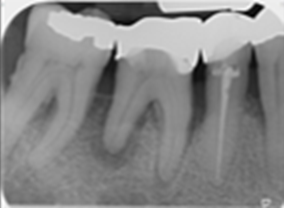

LR6: Root canal retreatment & internal root resorption management and cuspal coverage

Post Removal

12-Month Healing